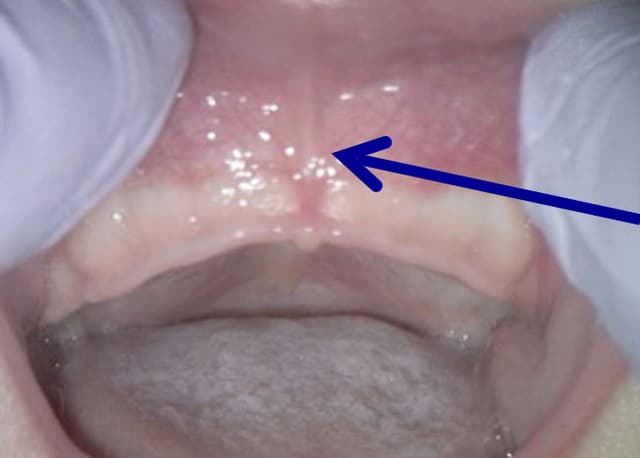

Posterior Tongue Tie

- Posterior tongue tie: Less visible, frenum restricted between floor of mouth and body of tongue, preventing optimized rest position

- Submucosal connective tissue fibers commonly present with posterior ties — critical that ALL restrictive fibers are identified and released